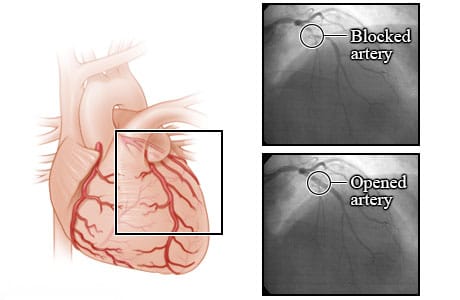

Arteries before and after an angioplasty

These X-rays show a blocked coronary artery before and after an angioplasty procedure. Before angioplasty, the blood flow is blocked by a narrowed artery. After the angioplasty, blood is flowing better through the newly opened artery. These X-rays are from an angiogram. An angiogram is a test that uses a special dye and camera to take X-ray pictures of the blood flow in an artery.